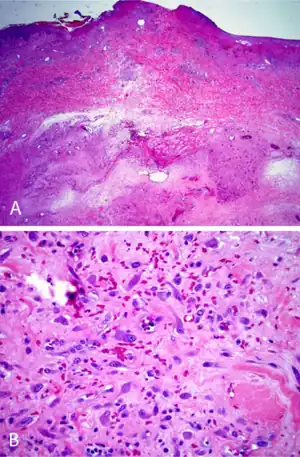

a,b)Decubital ischemic fasciitis H&E stain

On gross examination, IF tumors are typically white-yellow masses with central necrosis (i.e. areas of dead or dying cells), and areas containing cysts and/or old, dried hemorrhages.[6] The tumors are often poorly circumscribed, have an infiltrative appearance, may be multinodular, and lie in subcutaneous tissue but may also involve the dermal layer of the skin[8] and/or the reticular dermis.[6] Microscopic histopathological studies of IF tissues report the characteristic presence of a distinct zonal appearance, i.e. the presence of central zones of fibrinoid necrosis and areas of cyst-laden necrosis in a hypocellular background surrounding by a zone of granulation tissue (i.e. connective tissue containing microscopic blood vessels) populated by atypical, swollen fibroblasts, myofibroblasts, and/or macrophages.[4]